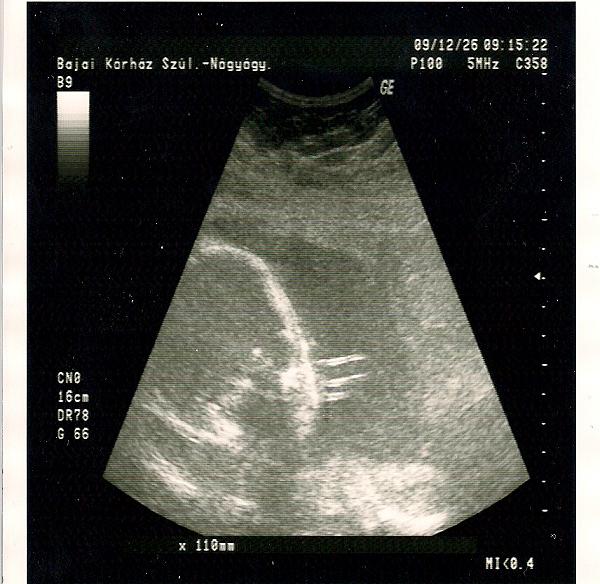

Talalkoztal ma Jolival a korhazban?...Drukkolok a köv heti UH miatt!!